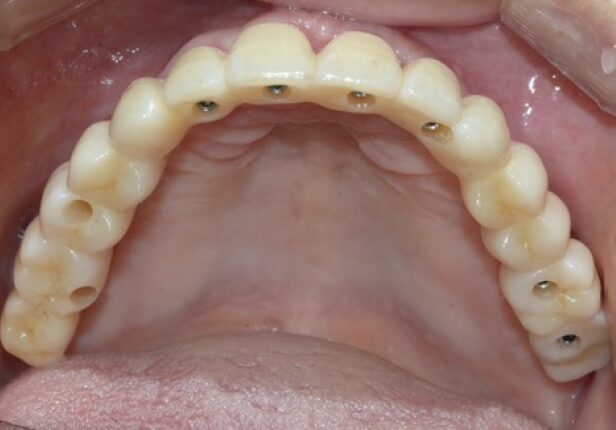

Maxilla Full Case Full case

Temporary Crown

Before Final Crown placement

Final Crown